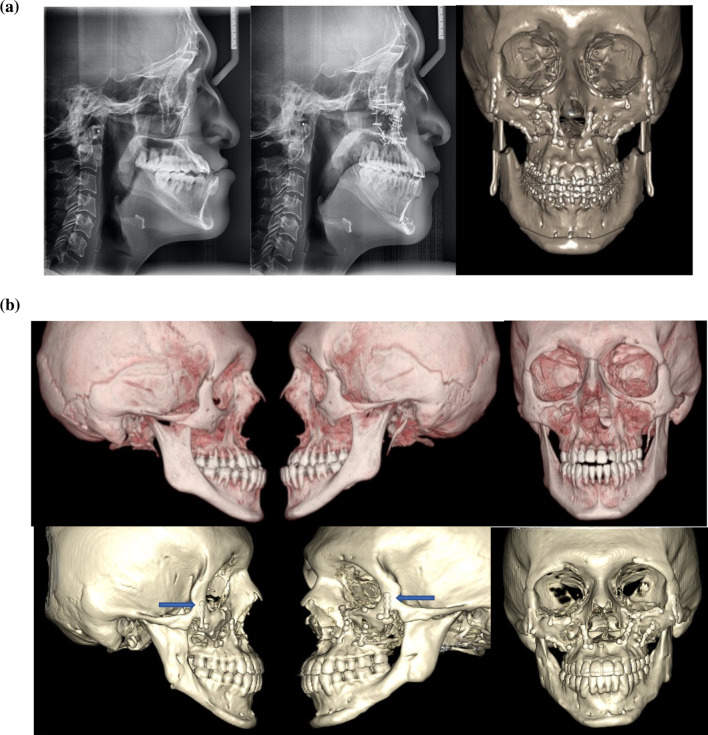

The CMLFIIIO was performed in a 35-year-old patient. The zygomatic osteotomy is symmetrically and easily performed in the 3d model as well as in the patient with the help of surgical guides (Fig. 14). If there is a vertical discrepancy between the left and right side of the face, it can be corrected without an additional Le Fort I osteotomy by ascending or descending the affected side.

Fig. 14.

Lateral views of the CT scan as well as frontal view. This is then printed, and then surgical splints are fabricated over the 3D model

In the 3d reconstruction of the patient’s CT scan at 4 years postop, it can be appreciated that the midface can have rigid fixation only at the zygomatic bone with one L-shaped plate on each side. The patient underwent a mandibular setback of 3 mm, genioplasty advancement of 7 mm and CMLFIIIO with a 4 mm advancement. In Fig. 15, the blue arrows show the bone gap. This is the reason why CMLFIIIO cannot have more than 5 mm in advancement. Also, a complete consolidation can be observed at the piriform rim (Fig. 15).

Fig. 15.

Postop lateral and frontal views of the CT scan. CMLFIIIO with symmetric osteotomies, adequate consolidation and bone modelling. Gaps remain at the zygomatic bone

24-year-old male patient with severe midface deficiency. The first surgery was a MAZLFIIIO with a 6 mm advancement through a coronal and transconjunctival approach. He had a posteroanterior discrepancy of 11 mm as shown in the preop lateral radiograph. On the second surgery, a 4 mm advancement Le Fort I osteotomy was performed along with an intraoral inverted L oblique modified osteotomy (IILOMO) with a 3 mm mandibular setback. A basal extended mentoplasty [16] (BEM) of 8 mm was also performed on the patient. The preop and postop lateral radiograph are shown. The 1-day postop CT scan with osteotomies and rigid internal fixation is also shown in Fig. 23a. The preop CT scan and the 2-year postop CT scan of the same patient are shown in Fig. 23b. A symmetric midface advancement with adequate bone consolidation is shown. The IILOMO is shown with adequate bone consolidation and the BEM adds harmony to the basal portion of the mandible without steps, appreciated in Fig. 23b.

Fig. 23.

a Pre- and post-operative lateral radiograph. Significant changes in the midface and lower third of the face can be seen. CT reconstruction immediately following the second surgery. A symmetric MAZLFIIIO can be appreciated along with a simultaneous repositioning of the maxilla, mandible and chin. b CT reconstruction in frontal and lateral views. 3D reconstruction at 2 years postop